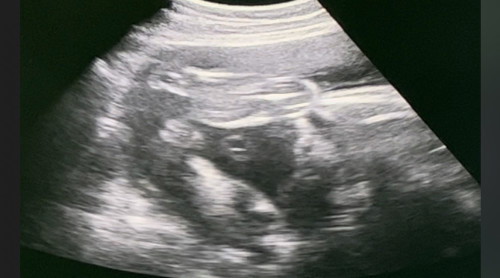

แม่ๆคิดว่าน้องเพศอะ ไรค่ะ คุณหมอบอกว่าผผู้หญิง แต่ บ้านนี้ไม่ค่อยแน่ใจค่ะ

น่าจะหญิงนะเหมือนกลีบ แต่รอดูเดือนหน้าอีกทีอาจจะหนีบไข่เลยดูเหมือน ญ